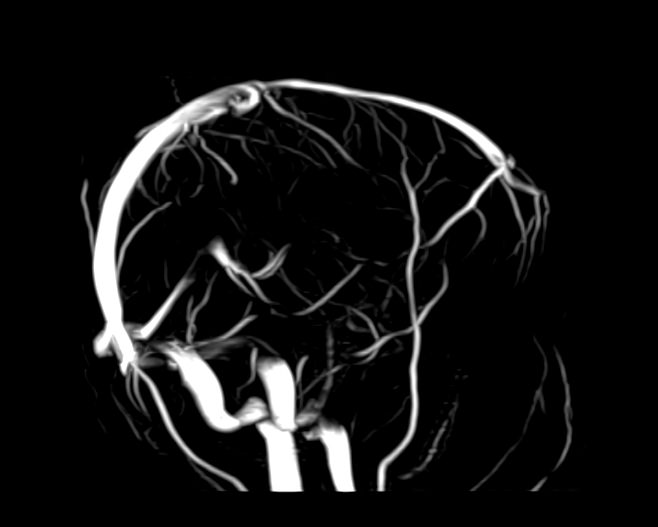

Магнитно-резонансная венография головного мозга позволяет детально изучить особенности анатомического и функциональной состояния венозного русла головного мозга. С помощью данного исследования можно исключить многие серьезные заболевания сосудов головного мозга и начать своевременное лечение.

Магнитно-резонансная томография вен применяется для диагностики широкого ряда заболеваний. В основе метода лежит воздействие магнитного излучения на ткани человека, что абсолютно безопасно и дает возможность с точностью визуализировать строение сосудов головного мозга.

По информативности МРТ артерий и вен головного мозга на шаг опережает традиционные способы диагностики с применением рентгеновских лучей или ультразвука. На МР-изображениях врачи-диагносты получают наглядную информацию о функционировании вен головного мозга.

МР-венография позволяет с высокой точностью определить:

• анатомический рисунок венозной системы;

• врожденные и приобретенные отклонения в строении и функционировании сосудов;

• нарушения трофики и оттока крови от отделов мозга;

• возможные повреждения сосудов и их последствия;

• наличие опухолевых образований, перекрывающих сосудистое русло.